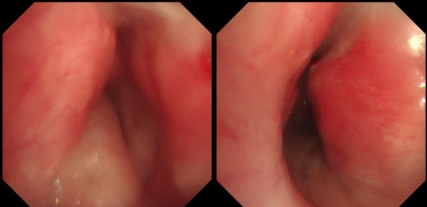

日前,患者趙先生(化名)因進行性呼吸困難來到河南省胸科醫(yī)院尋求治療,經(jīng)檢查確診為支氣管結(jié)核導致氣管中下段重度瘢痕性狹窄,最窄處直徑僅約3mm,且局部軟骨環(huán)破壞、塌陷,這意味著支撐氣道的結(jié)構(gòu)遭到損毀,通氣功能嚴重受損,且因狹窄部位靠近隆突,治療操作風險極高,稍有不慎就可能導致大出血、氣道完全閉塞等致命并發(fā)癥。

在硬質(zhì)支氣管鏡引導下,手術(shù)團隊首先對狹窄部位進行球囊擴張。隨后,將術(shù)前根據(jù)患者三維CT數(shù)據(jù)定制的Y型硅酮支架精準覆蓋于氣管狹窄段。該支架確保與患者自身的氣道解剖結(jié)構(gòu)完美貼合,實現(xiàn)最佳支撐效果,并最大限度減少粘膜刺激增生等特點。支架展開后穩(wěn)定支撐于隆突及雙側(cè)主支氣管,氣道狹窄立即得到解除。

隨著手術(shù)順利完成,趙先生蘇醒后自覺呼吸順暢,術(shù)后復查顯示支架位置良好,氣道通暢,呼吸困難癥狀顯著緩解。